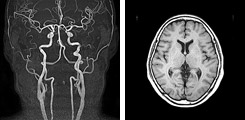

乳がんMRI検査:18,000円

乳がんを診断するための乳腺MRI(3.0テスラ検査)、最も病変発見率の高い画像診断です。放射線科専門医による結果説明があります。(後日金曜日)

※妊娠中の方、ペースメーカー挿入中の方はご相談ください。